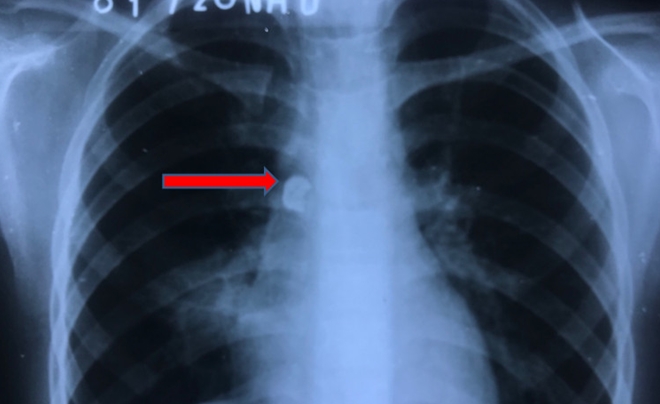

Hình ảnh X-quang phổi cho thấy dị vật nằm bên phải cạnh cột sống

Hai ngày đầu, trẻ sinh hoạt, học tập bình thường, những ngày sau, trẻ ho vài lần, người nhà đưa trẻ đi khám tư, uống thuốc 2 đợt vẫn không hết nên được bác sĩ cho đi chụp hình X-quang phổi. Ghi nhận dị vật cản quang nên đề nghị người nhà cho trẻ nhập viện, gia đình tức tốc đưa trẻ nhập bệnh viện Nhi đồng TP Hồ Chí Minh.

Tại đây, các bác sĩ đã tiến hành nội soi phế quản gắp ra được chiếc răng 1 x 1 x 1 cm, chân răng cắm sâu vào thành phế quản trung gian phải, gây không ít khó khăn khi gắp. Sau 30 phút can thiệp, các bác sĩ đã lấy được chiếc răng ra khỏi đường thở của em bé trong sự thở phào nhẹ nhõm. Chiếc răng to, chiếm hết lòng phế quản góc phải, bám chặt vào thành phế quản, gây ra nguy cơ thủng phế quản khi nội soi can thiệp. Sau gắp dị vật trẻ được chuyển khoa hồi sức ngoại điều trị tiếp một ngày, sau đó cai máy thở, tỉnh táo.